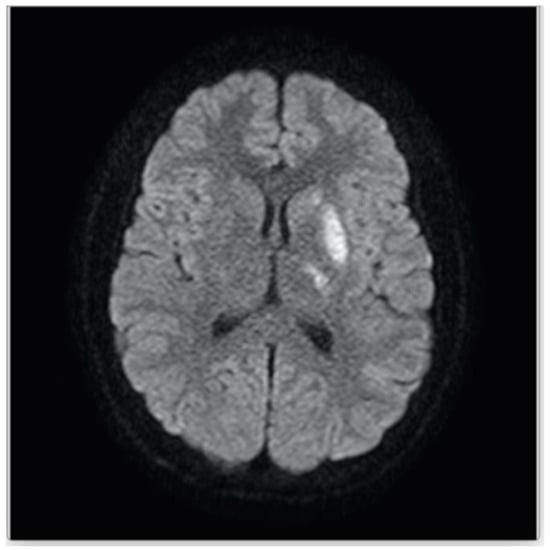

2. Patient Description

| Baumgartle * | 2016 | M/12 years old | Headache, facial drooping, slurred speech and right sided weakness | Left MCA infarction |